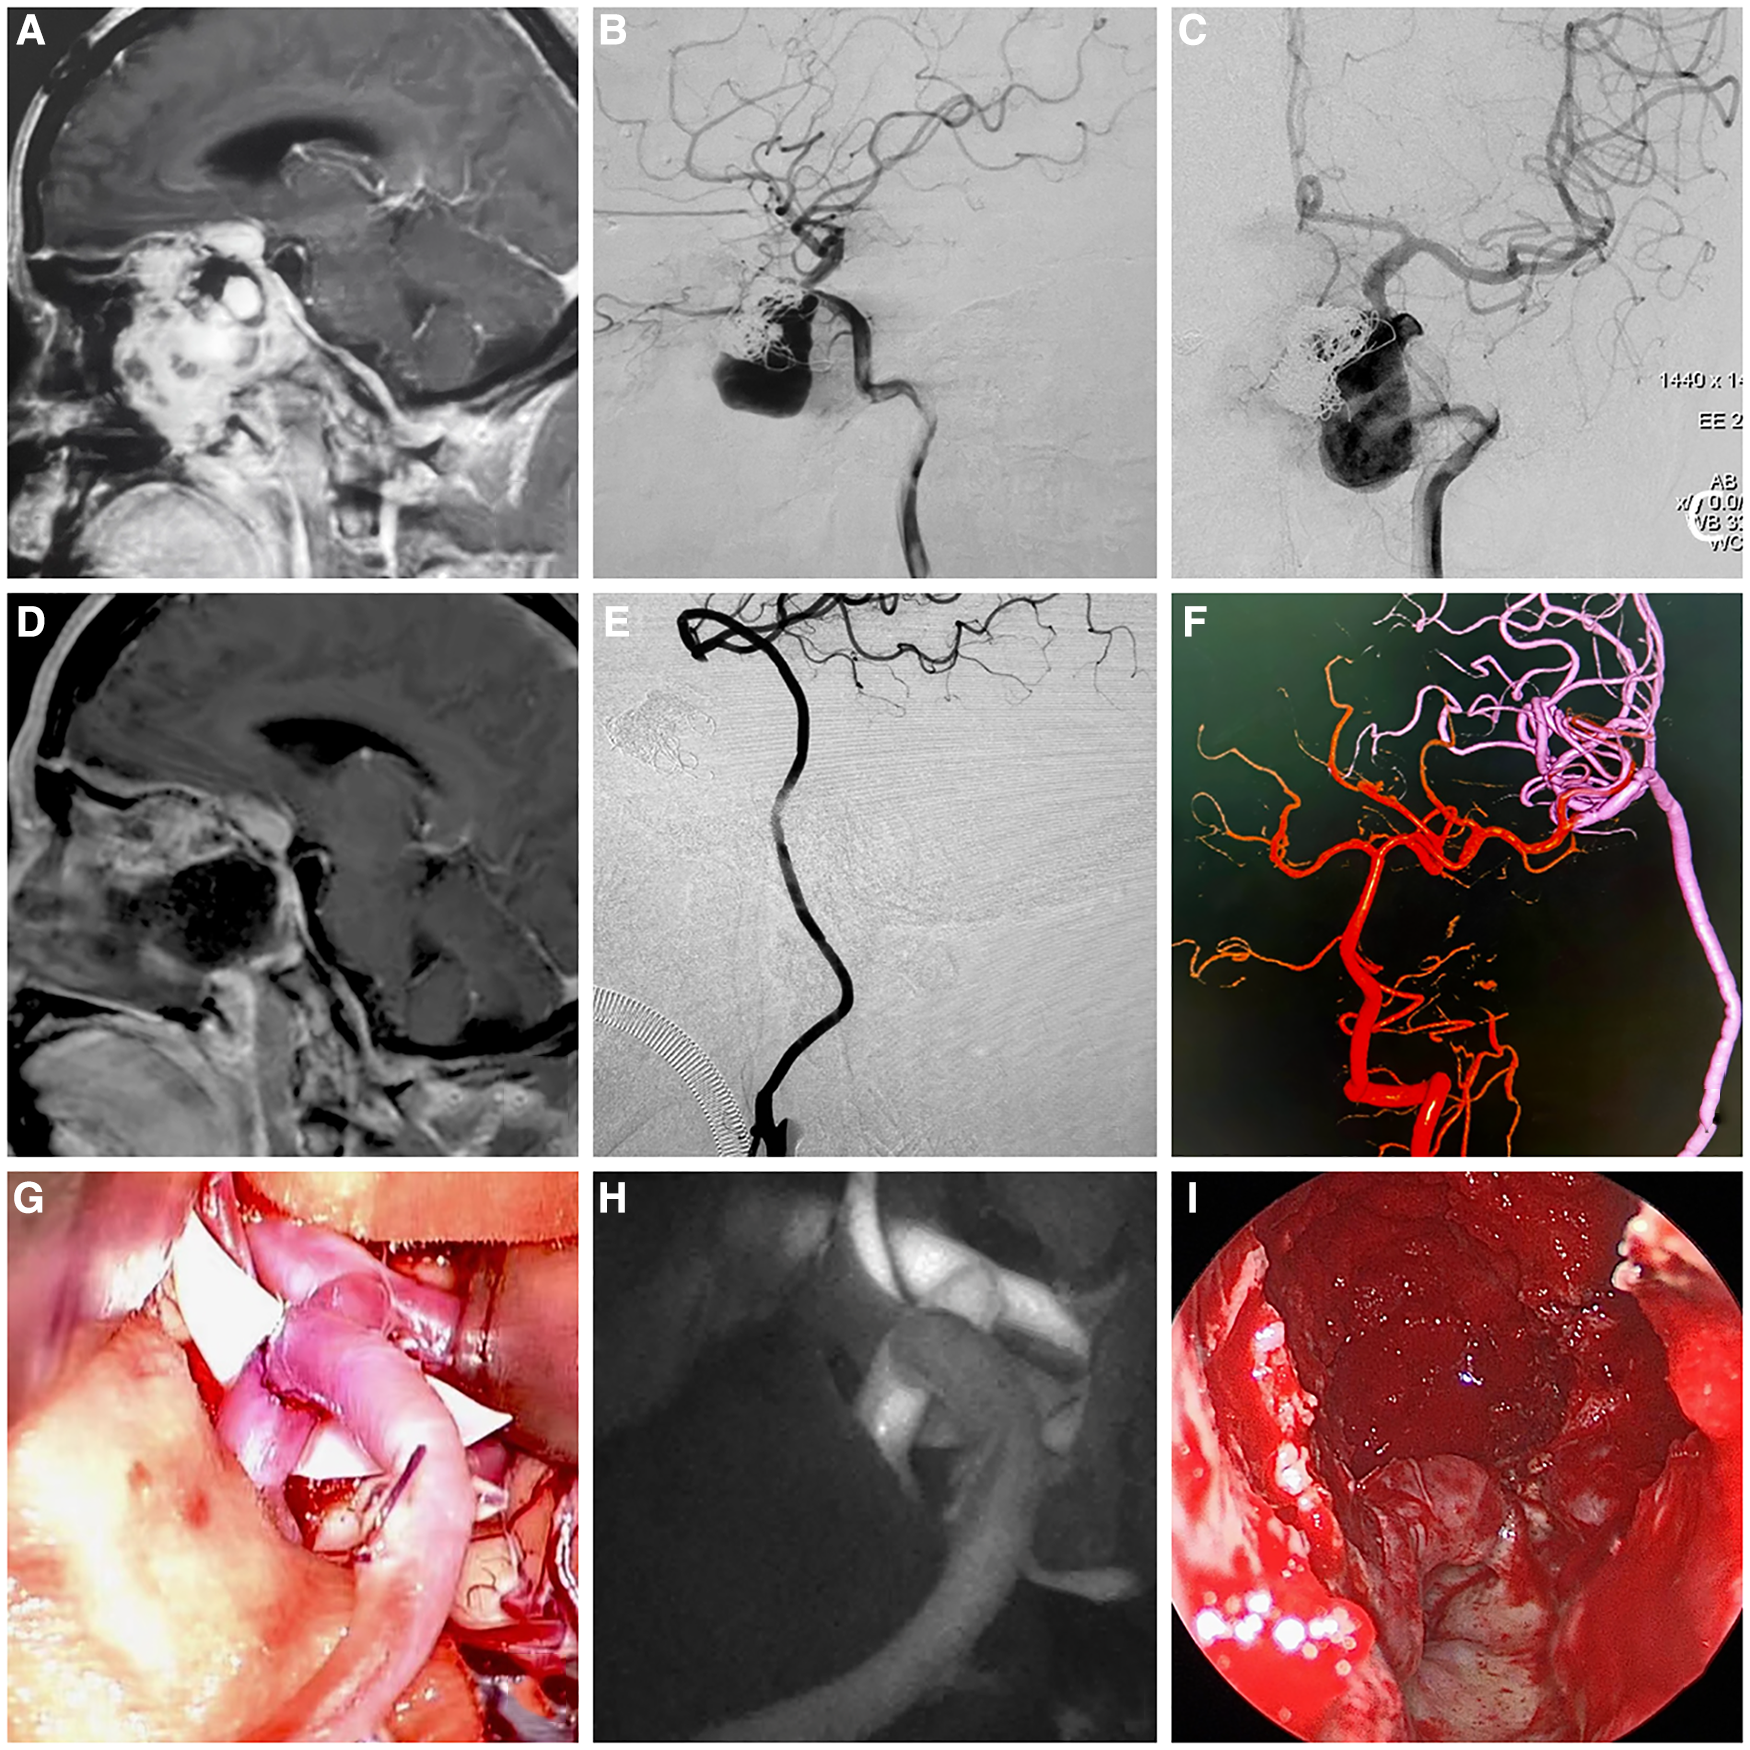

In this study, intraoperative fluorescein angiography showed good patency of the radial artery graft in 10 patients, and postoperative CTA and DSA also revealed good patency of the reconstructed vessels and no blood flow in the excluded vessels. In addition, CTP showed no cerebral hypoperfusion on the reconstructed side after surgery. In terms of tumor resection, contrast-enhanced MRI of the brain confirmed total resection in eight cases, subtotal resection in one case, and partial resection in one case. Figures 1 and 2 are typical preoperative and postoperative images of a patient who underwent Fukushima bypass type I and a patient who underwent Fukushima bypass type III, respectively.

Images of a patient with recurrent fibrous dysplasia combined with internal carotid artery aneurysm who received Fukushima bypass type III (ECA-RA-M2) combined with transnasal endoscopic surgery to remove the affected bone, achieved optic nerve decompression and resection of the left internal carotid artery aneurysm. (A) Preoperative enhanced cranial magnetic resonance imaging (MRI) showing the internal carotid artery was invaded, and an aneurysm was formed. (B, C) Preoperative lateral and front digital subtraction angiography (DSA) projections showing the internal carotid artery and aneurysm. (D) Postoperative enhanced cranial MRI showing subtotal resection of the tumor and adequate decompression. (E, F) Postoperative cerebral DSA showing good patency of the radial artery graft, no visualization of ICA-C1 to ICA-C4 segments, and anterior cerebral circulation blood supply from posterior cerebral circulation. (G) Intraoperative image of Fukushima bypass type III (ECA-RA-M2). (H) Intraoperative fluorescein angiography showing good patency of the radial artery graft. (I) Intraoperative images of endoscopic subtotal resection of tumors.